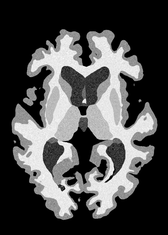

4.2 Registration to a 100 micron ex-vivo brain MRI volume

To showcase the efficacy of our method on real large scale images, we register a 250 in-vivo MRI image (Lüsebrink et al., 2017) to a 100 ex-vivo FLASH human brain volume (Edlow et al., 2019). This represents an inverse problem with more than 11.2B optimizable parameters (compared to 20M for clinical datasets), or 44.8GB of GPU memory. The entire problem does not fit on most GPUs, necessitating distributed multimodal registration. We optimize a composite transform - affine followed by a diffeomorphic mapping; details can be found in Section E.1. Multimodal deformable registration took 58 seconds on 8 NVIDIA A6000 GPUs, which is unprecedented at this resolution. Fig. 6 shows qualitative results, highlighting the ability to register highly detailed structures such as cerebellar white matter; these structures are not visible at macroscopic scales. The resultant advantages of performing registration at this scale can allow researchers to characterize the neuroanatomy at microscopic resolutions and allow morphometric analysis of cortical layers and subcortical nuclei among other structures.